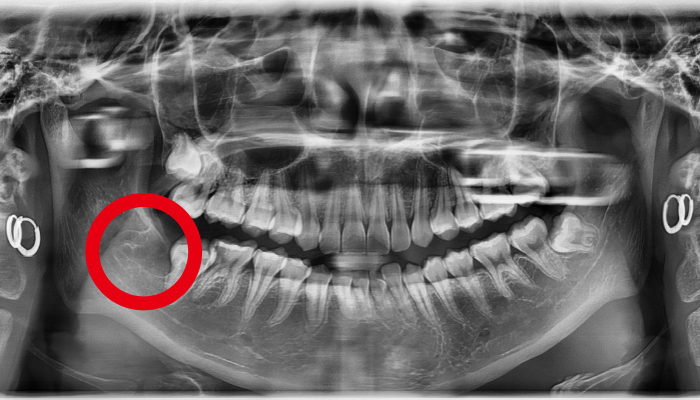

사랑니 발치 전후 사례

• 치료전

치료후